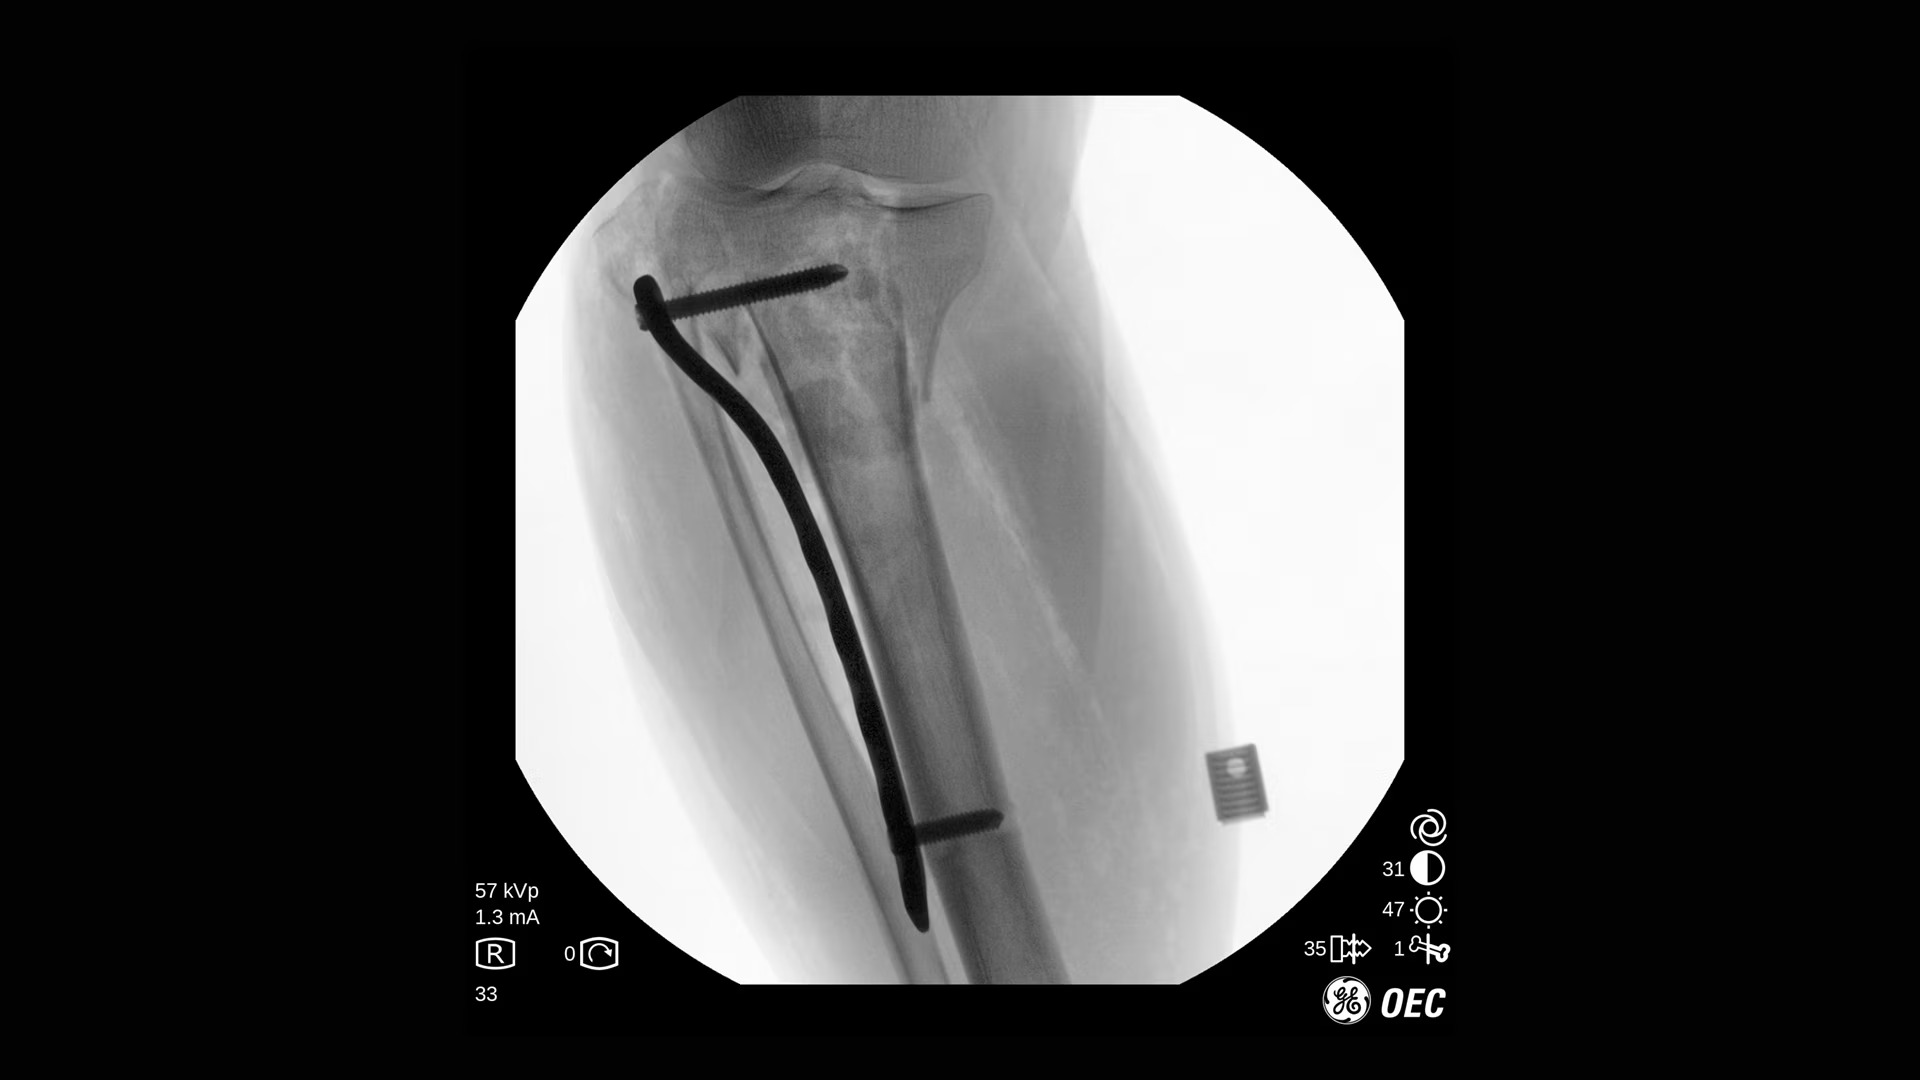

GE Healthcare OEC One CFD относится к классу мобильных рентгеновских аппаратов с С-образной дугой, в которых все ключевые узлы — излучатель, детектор, монитор и панель управления — объединены в единую компактную конструкцию. КМОП-плоскопанельный детектор и фирменная цепочка обработки Clear View обеспечивают высокую детализацию изображения в широком спектре клинических задач: от рутинных травматолого-ортопедических вмешательств до эндоваскулярных процедур и сложной спинальной хирургии. Интеллектуальные алгоритмы подавления помех от металлоконструкций, автоматической оптимизации окна и уровня, а также режимы увеличения позволяют уверенно визуализировать мелкие структуры, проводники и импланты без существенного роста дозовой нагрузки.

- Интеллектуальные алгоритмы обработки изображения (в том числе подавление помех от металлоконструкций и автоматический выбор окна/уровня).

- Функции Live Zoom и работа с последней рентгеноскопической последовательностью для снижения количества повторных экспозиций.

- Специализированные клинические профили для ортопедии, спинальной хирургии, общей хирургии, урологии, сосудистых и болевых процедур.